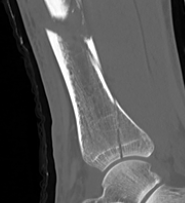

Posterior Malleolar Fractures

- occult in 70%

- especially with spiral distal tibial fractures